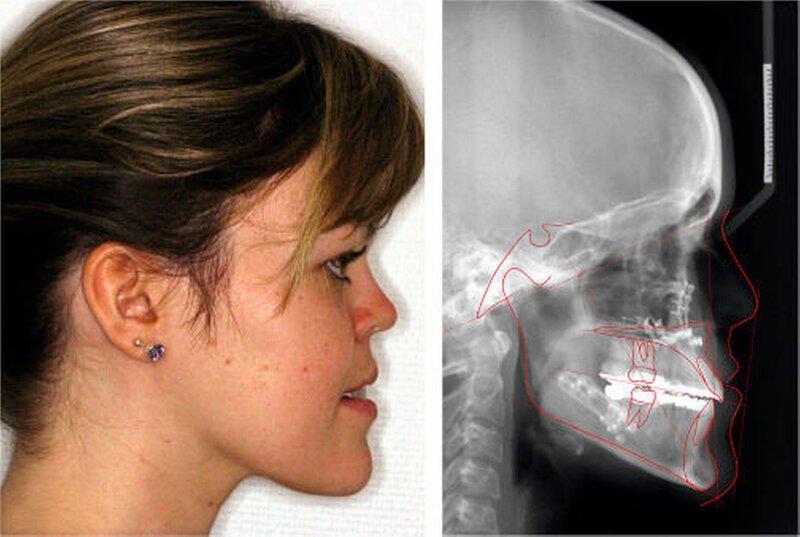

Die Patientin war zu Behandlungsbeginn 26 Jahre alt. Sie wies eine ausgeprägte skelettale Mesialbisslage (Wits: – 15,6 mm) mit retrognather Maxilla (SNA: 76°) und prognather Mandibula (SNB 87°) bei zusätzlicher Mittelgesichtshypoplasie auf (Abbildung 1a). Intraoral bestanden ein frontal offener Biss und eine transversale Enge im Oberkiefer mit zirkulärem Kreuzbiss (Abbildung 1b).

Die Planung der bimaxillären Umstellungsosteotomie erfolgte mittels Modell-Operation und Simulation am Fernröntgenseitenbild (fr-win, Computer konkret, Falkenstein) (Abbildung 5).

Die Maxilla wurde intraoperativ 3 mm vorverlagert, 3 mm posterior impaktiert und transversal 2 mm erweitert. Die Mandibula wurde mittels sagittaler Spaltung nach Obwegeser/Dal Pont 4 mm rückverlagert. Abbildung 6 zeigt den postoperativen Befund am Fernröntgenseitenbild und von extraoral lateral.